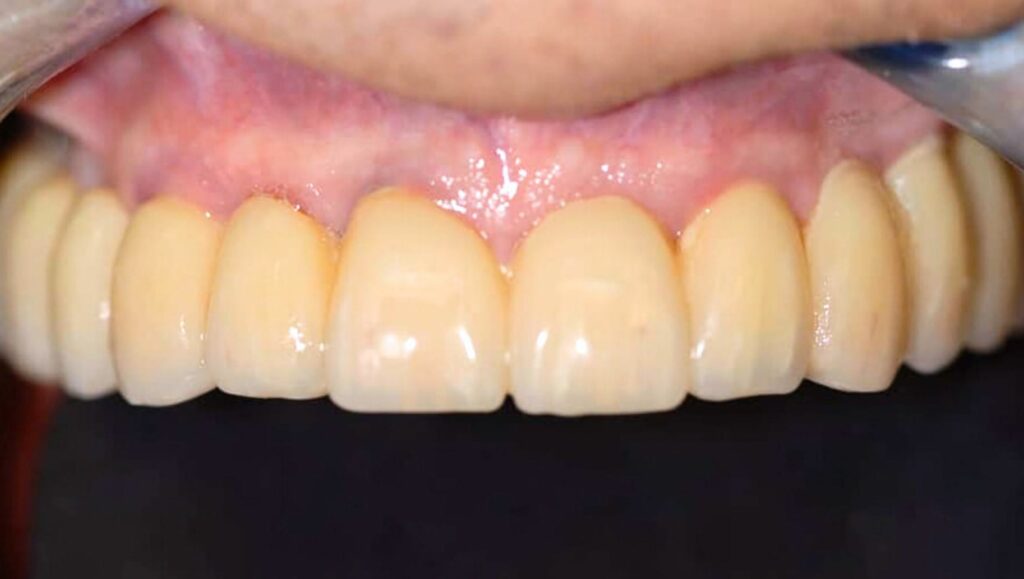

Al paziente, sempre sotto in sedazione cosciente, sono stati rimossi i denti interessati ed inseriti gli impianti. Con un carico immediato nel giro 24 ore sono state posizionate le corone provvisorie avvitate sugli impianti con un risultato estetico molto soddisfacente.

Sottolineiamo la situazione di partenza ed il risultato finale: